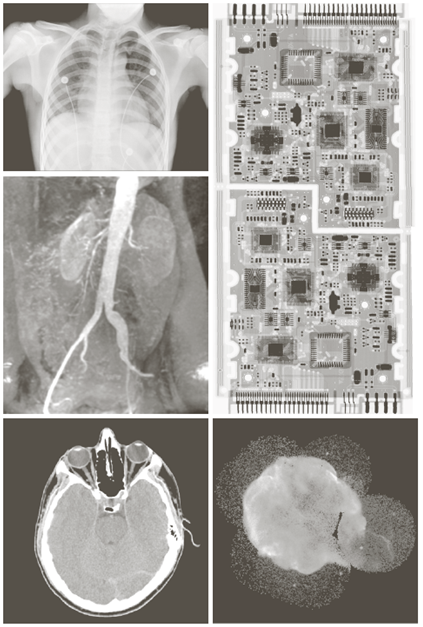

X-ray image

a) 항암제 Taxol b) 콜레스테롤 c) 마이크로프로세서

a) 회로 기판